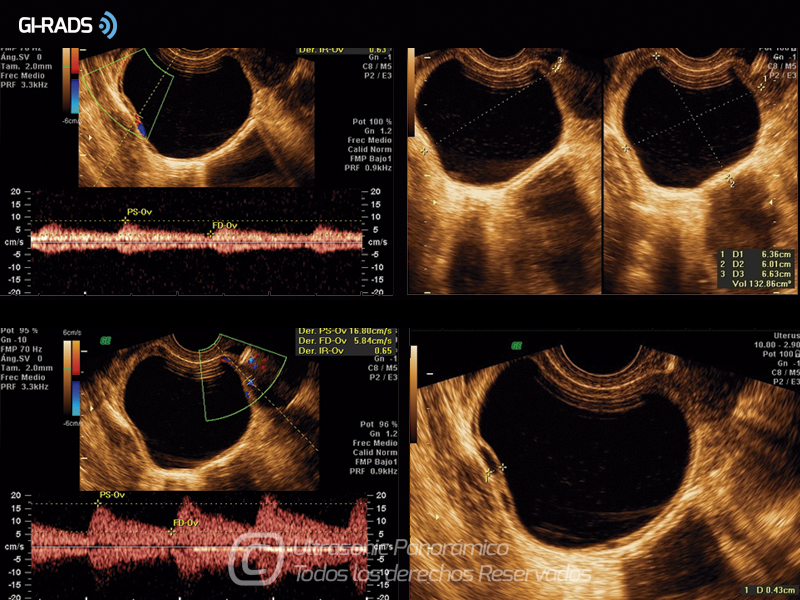

• Patologías Benignas – Cistoadenoma